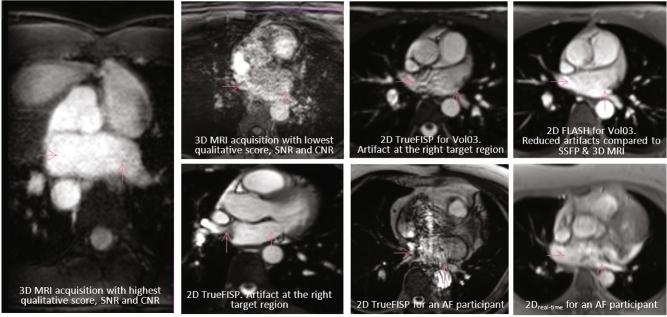

Magnetic resonance imaging (MRI) guided cardiac radioablation (CR) for atrial fibrillation (AF) is a promising treatment concept. However, the visibility of AF CR targets on MRI acquisitions requires further exploration and MRI sequence and parameter optimization has not yet been performed for this application. This pilot study explores the feasibility of MRI-guided tracking of AF CR targets by evaluating AF CR target visualization on human participants using a selection of 3D and 2D MRI sequences.MRI datasets were acquired in healthy and AF participants using a range of MRI sequences and parameters. MRI acquisition categories included 3D free-breathing acquisitions (3D), 2D breath-hold ECG-gated acquisitions (2D), stacks of 2D breath-hold ECG-gated acquisitions which were retrospectively interpolated to 3D datasets (3D), and 2D breath-hold ungated acquisitions (2D). The ease of target delineation and the presence of artifacts were qualitatively analyzed. Image quality was quantitatively analyzed using signal-to-noise ratio (SNR), contrast-to-noise ratio (CNR) and non-uniformity. Confident 3D target delineation was achievable on all 3D datasets but was not possible on any of the 3D datasets. Fewer artifacts and significantly better SNR, CNR and non-uniformity metrics were observed with 3D compared to 3D. 2D datasets had slightly lower SNR and CNR than 2D and 3D datasets. AF CR target visualization on MRI was qualitatively and quantitatively evaluated. The study findings indicate that AF CR target visualization is achievable despite the imaging challenges associated with these targets, warranting further investigation into MRI-guided AF CR treatments.

磁共振成像(MRI)引导下的心房颤动(AF)心脏射频消融术(CR)是一个很有前景的治疗概念。然而,AF CR靶点在MRI图像上的可视性仍需进一步探索,且针对该应用的MRI序列和参数优化尚未开展。这项初步研究通过使用一系列3D和2D MRI序列评估人类受试者的AF CR靶点可视化情况,探讨MRI引导下追踪AF CR靶点的可行性。使用一系列MRI序列和参数,在健康受试者和AF患者中采集MRI数据集。MRI采集类别包括3D自由呼吸采集(3D)、2D屏气心电图门控采集(2D)、将回顾性插值的2D屏气心电图门控采集堆叠成3D数据集(3D)以及2D屏气非门控采集(2D)。对靶点勾画的难易程度和伪影的存在情况进行定性分析。使用信噪比(SNR)、对比噪声比(CNR)和不均匀性对图像质量进行定量分析。在所有3D数据集上都能实现可靠的3D靶点勾画,但在任何3D数据集上都无法实现。与3D相比,3D观察到的伪影更少,SNR、CNR和不均匀性指标明显更好。2D数据集的SNR和CNR略低于2D和3D数据集。对MRI上的AF CR靶点可视化进行了定性和定量评估。研究结果表明,尽管与这些靶点相关的成像存在挑战,但AF CR靶点可视化是可以实现的,这值得对MRI引导的AF CR治疗进行进一步研究。